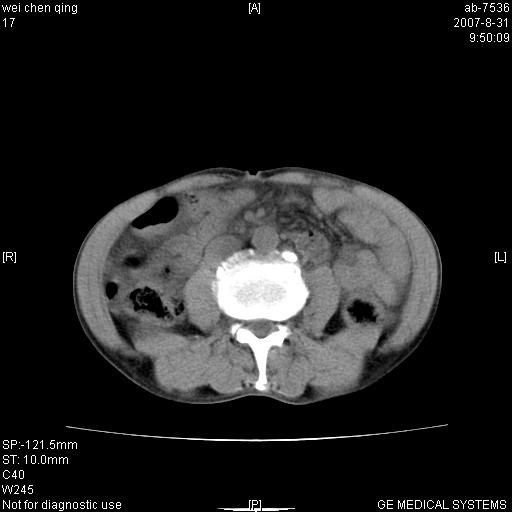

以下是引用zyyzzy在2007-8-31 14:34:00的发言:[br]该病人肝内胆管扩张,胆囊及胆总管未见明显扩张。在倒数第9层图像上可看到左右肝管结合部(肝总管)有软组织影,此处应薄层扫描。考虑肝总管占位(ca)、腹水。[br]